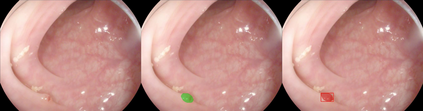

Early detection, accurate segmentation, classification and tracking of polyps during colonoscopy are critical for preventing colorectal cancer. Many existing deep-learning-based methods for analyzing colonoscopic videos either require task-specific fine-tuning, lack tracking capabilities, or rely on domain-specific pre-training. In this paper, we introduce \textit{PolypSegTrack}, a novel foundation model that jointly addresses polyp detection, segmentation, classification and unsupervised tracking in colonoscopic videos. Our approach leverages a novel conditional mask loss, enabling flexible training across datasets with either pixel-level segmentation masks or bounding box annotations, allowing us to bypass task-specific fine-tuning. Our unsupervised tracking module reliably associates polyp instances across frames using object queries, without relying on any heuristics. We leverage a robust vision foundation model backbone that is pre-trained unsupervisedly on natural images, thereby removing the need for domain-specific pre-training. Extensive experiments on multiple polyp benchmarks demonstrate that our method significantly outperforms existing state-of-the-art approaches in detection, segmentation, classification, and tracking.